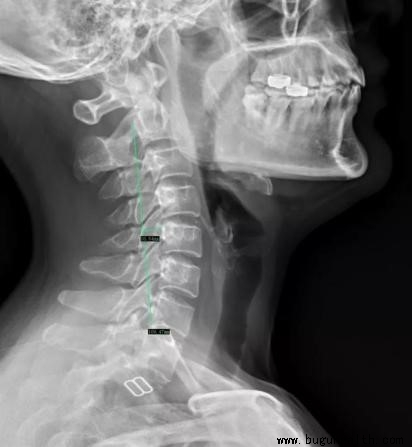

所谓生理曲度说的是脊柱矢状位上的曲线,那么测量时最多被选择作为观察的就是脊柱侧位片。这里就脊柱的四个曲度测量介绍几种简便快捷的测量方法。

颈椎:Borden氏测量法,即自枢椎齿突后上缘到C7椎体后下缘画一直线,使椎体后缘与连线成一相应的自然弧,C5椎体后上缘为弧的顶点,弧最大垂直深度为(12±5)mm;当此数值 > 17mm 为曲度增大,< 7mm 为变直,< 0mm 为反弓。